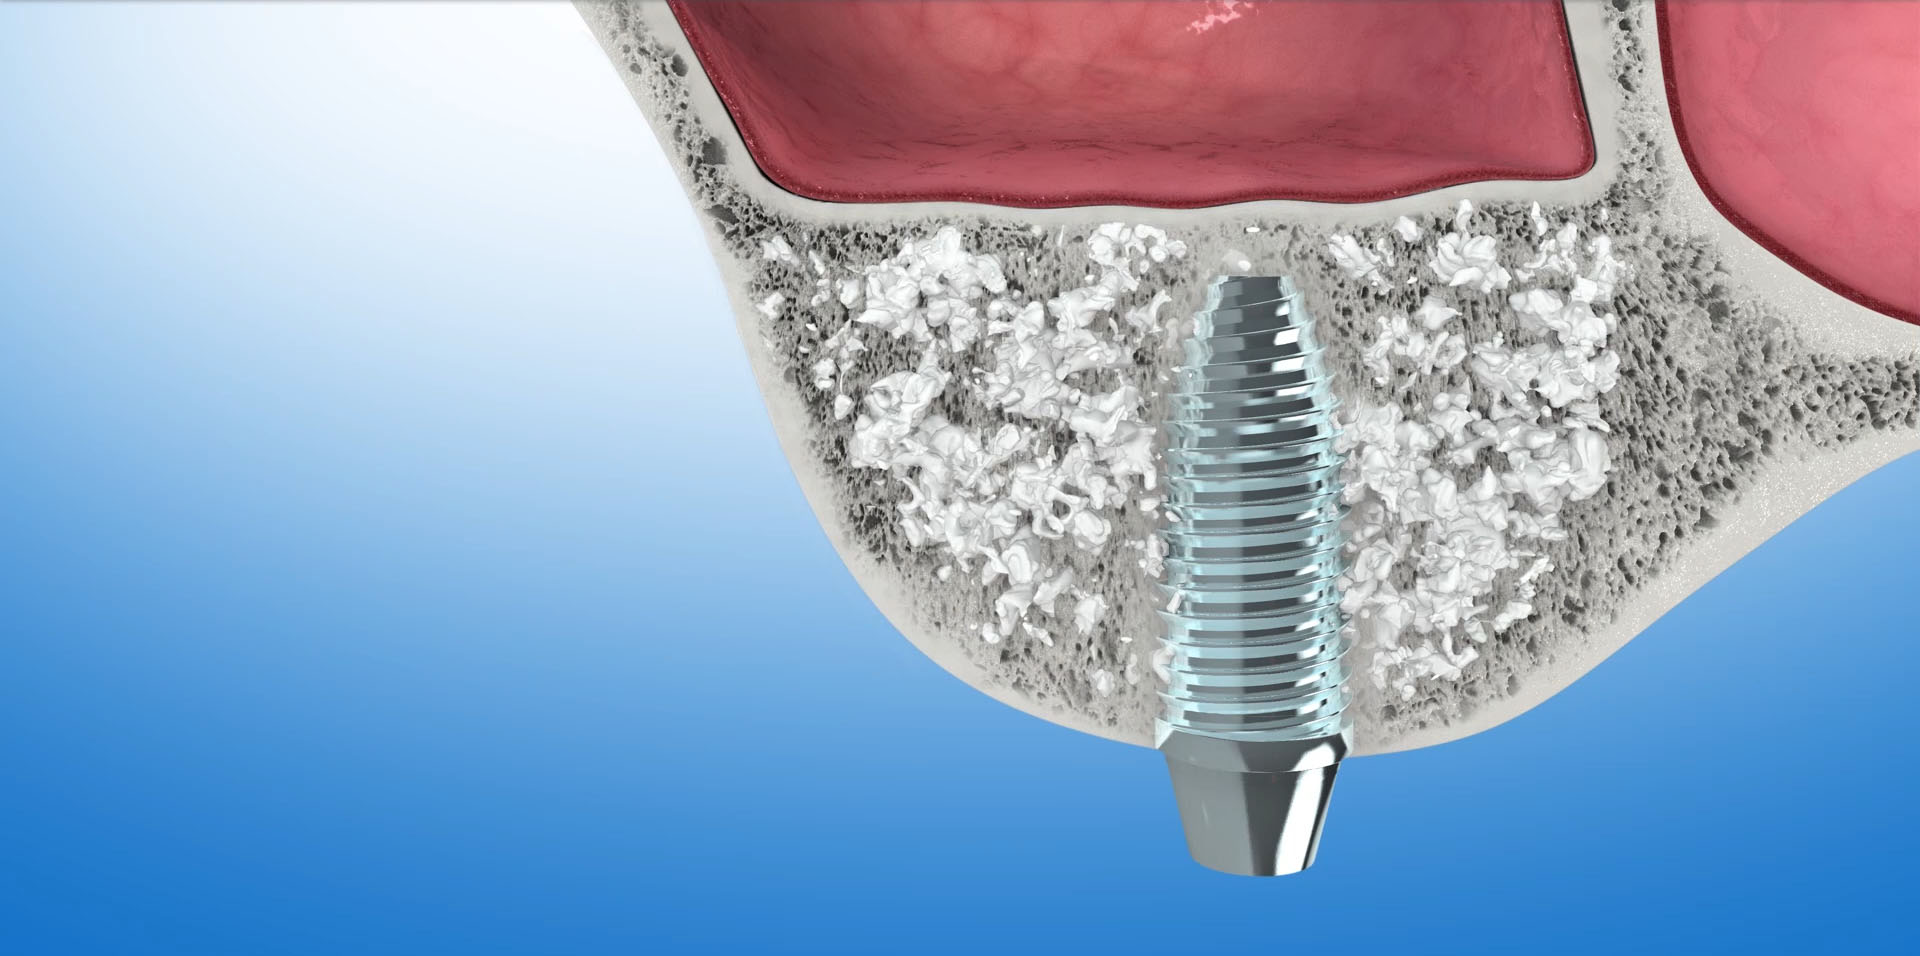

STEROWANA REGENERACJA KOŚCI (GBR-guided bone regeneration)

To odbudowa kości pacjenta do poziomu umożliwiającego implantację. Zanik kości wyrostka w wymiarze pionowym i poziomym powoduje powoduje w efekcie to, że jest on za niski lub zbyt wąski aby można było umieścić w nim implant dentystyczny. Ok. 40% przypadków wszystkich zabiegów implantacyjnych wymaga regeneracji kości. W jej wyniku odbudowana kość będzie stanowiła odpowiednie oparcie dla implantu oraz znacząco poprawi wynik estetyczny leczenia.

Do sterowanej regeneracji kości wykorzystywane są biomateriały – czyli substytuty kości oraz kość własną pacjenta. Często używane są równocześnie. Do pokrycia augumentatu czyli materiału odbudowującego kość używamy specjalnych membran, które stanowią barierę dla tkanek miękkich. Ogromna różnorodność na rynku biomateriałów pozwala na optymalny wybór w każdym konkretnym przypadku. W naszej Praktyce, zdecydowana większość zabiegów odbudowy kości przeprowadzana jest z zastosowaniem materiału kościozastępczego Bio-Oss oraz kolagenowych resorbowalnych membran Bio-Gide firmy Geistlich.

Bio-Oss

To materiał kościozastępczy produkowany z kości wołowych. W trakcie procesu produkcyjnego usuwane są z niego wszystkie składniki mogące powodować przenoszenie chorób lub wywoływać reakcje alergiczne. Naturalna struktura mineralna zostaje jednak nienaruszona. Wykazuje ona ogromne podobieństwo do struktury kości ludzkiej. Ten porowaty materiał o utkaniu ludzkiej kości stanowi doskonałe rusztowanie dla naczyń krwionośnych i komórek kościotwórczych. Stanowi matrycę, sieć dla tworzącej się tkanki kostnej. Z upływem czasu, ok.1mm w ciągu miesiąca, Bio-Oss ulega resorbcji, a miejsce po nim zajmuje nowo wytworzona kość.

Bio-Gide

To membrana zbudowana z oczyszczonych włókien kolagenowych. Stanowi ona barierę nie pozwalającą na kontakt tkanek miękkich z materiałem kościozastępczym. Prócz tego wspomaga proces gojenia się tkanki kostnej i tkanek miękkich.